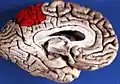

Medial surface of left cerebral hemisphere. (Precuneus visible at top left.) (Anterior to the right.)

In neuroanatomy, the precuneus is the portion of the superior parietal lobule on the medial surface of each brain hemisphere. It is located in front of the cuneus (the upper portion of the occipital lobe). The precuneus is bounded in front by the marginal branch of the cingulate sulcus, at the rear by the parieto-occipital sulcus, and underneath by the subparietal sulcus. It is involved with episodic memory, visuospatial processing, reflections upon self, and aspects of consciousness.